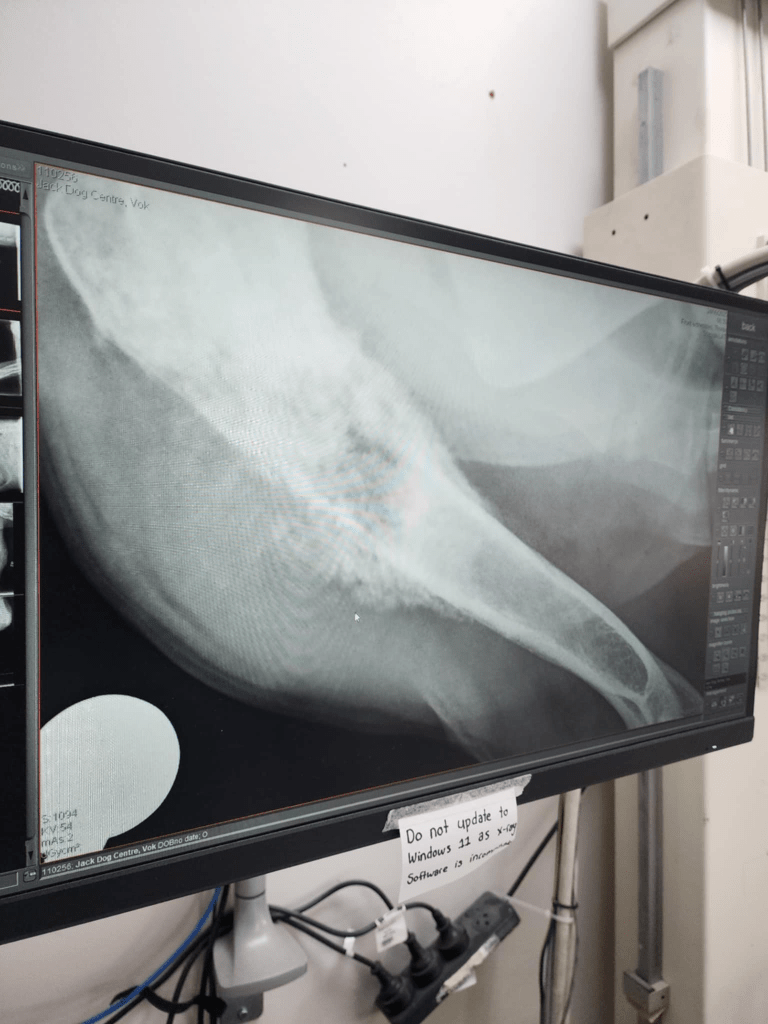

Half an hour later, we have been called to come back to look at the X rays. The presentation is consistent with osteosarcoma. His leg is at the point of fracturing.

The only good news is that it didn’t spread, yet. His lungs are clear; his heart is fine. He is still a candidate for leg removal surgery. This is his only chance, provided that the blood work comes back fine for surgery.